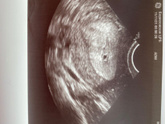

Девочки у кого такое было.? 11,12,13 октября были месячные. 25 октября отследила по тестам овуляцию. 5 ноября тест показал 2 полоски , вторая бледная. 9 ноября пошла к врачу , узи она не назначила, сказала что рано, отправила на ХГЧ , что бы по нему … Читать далее